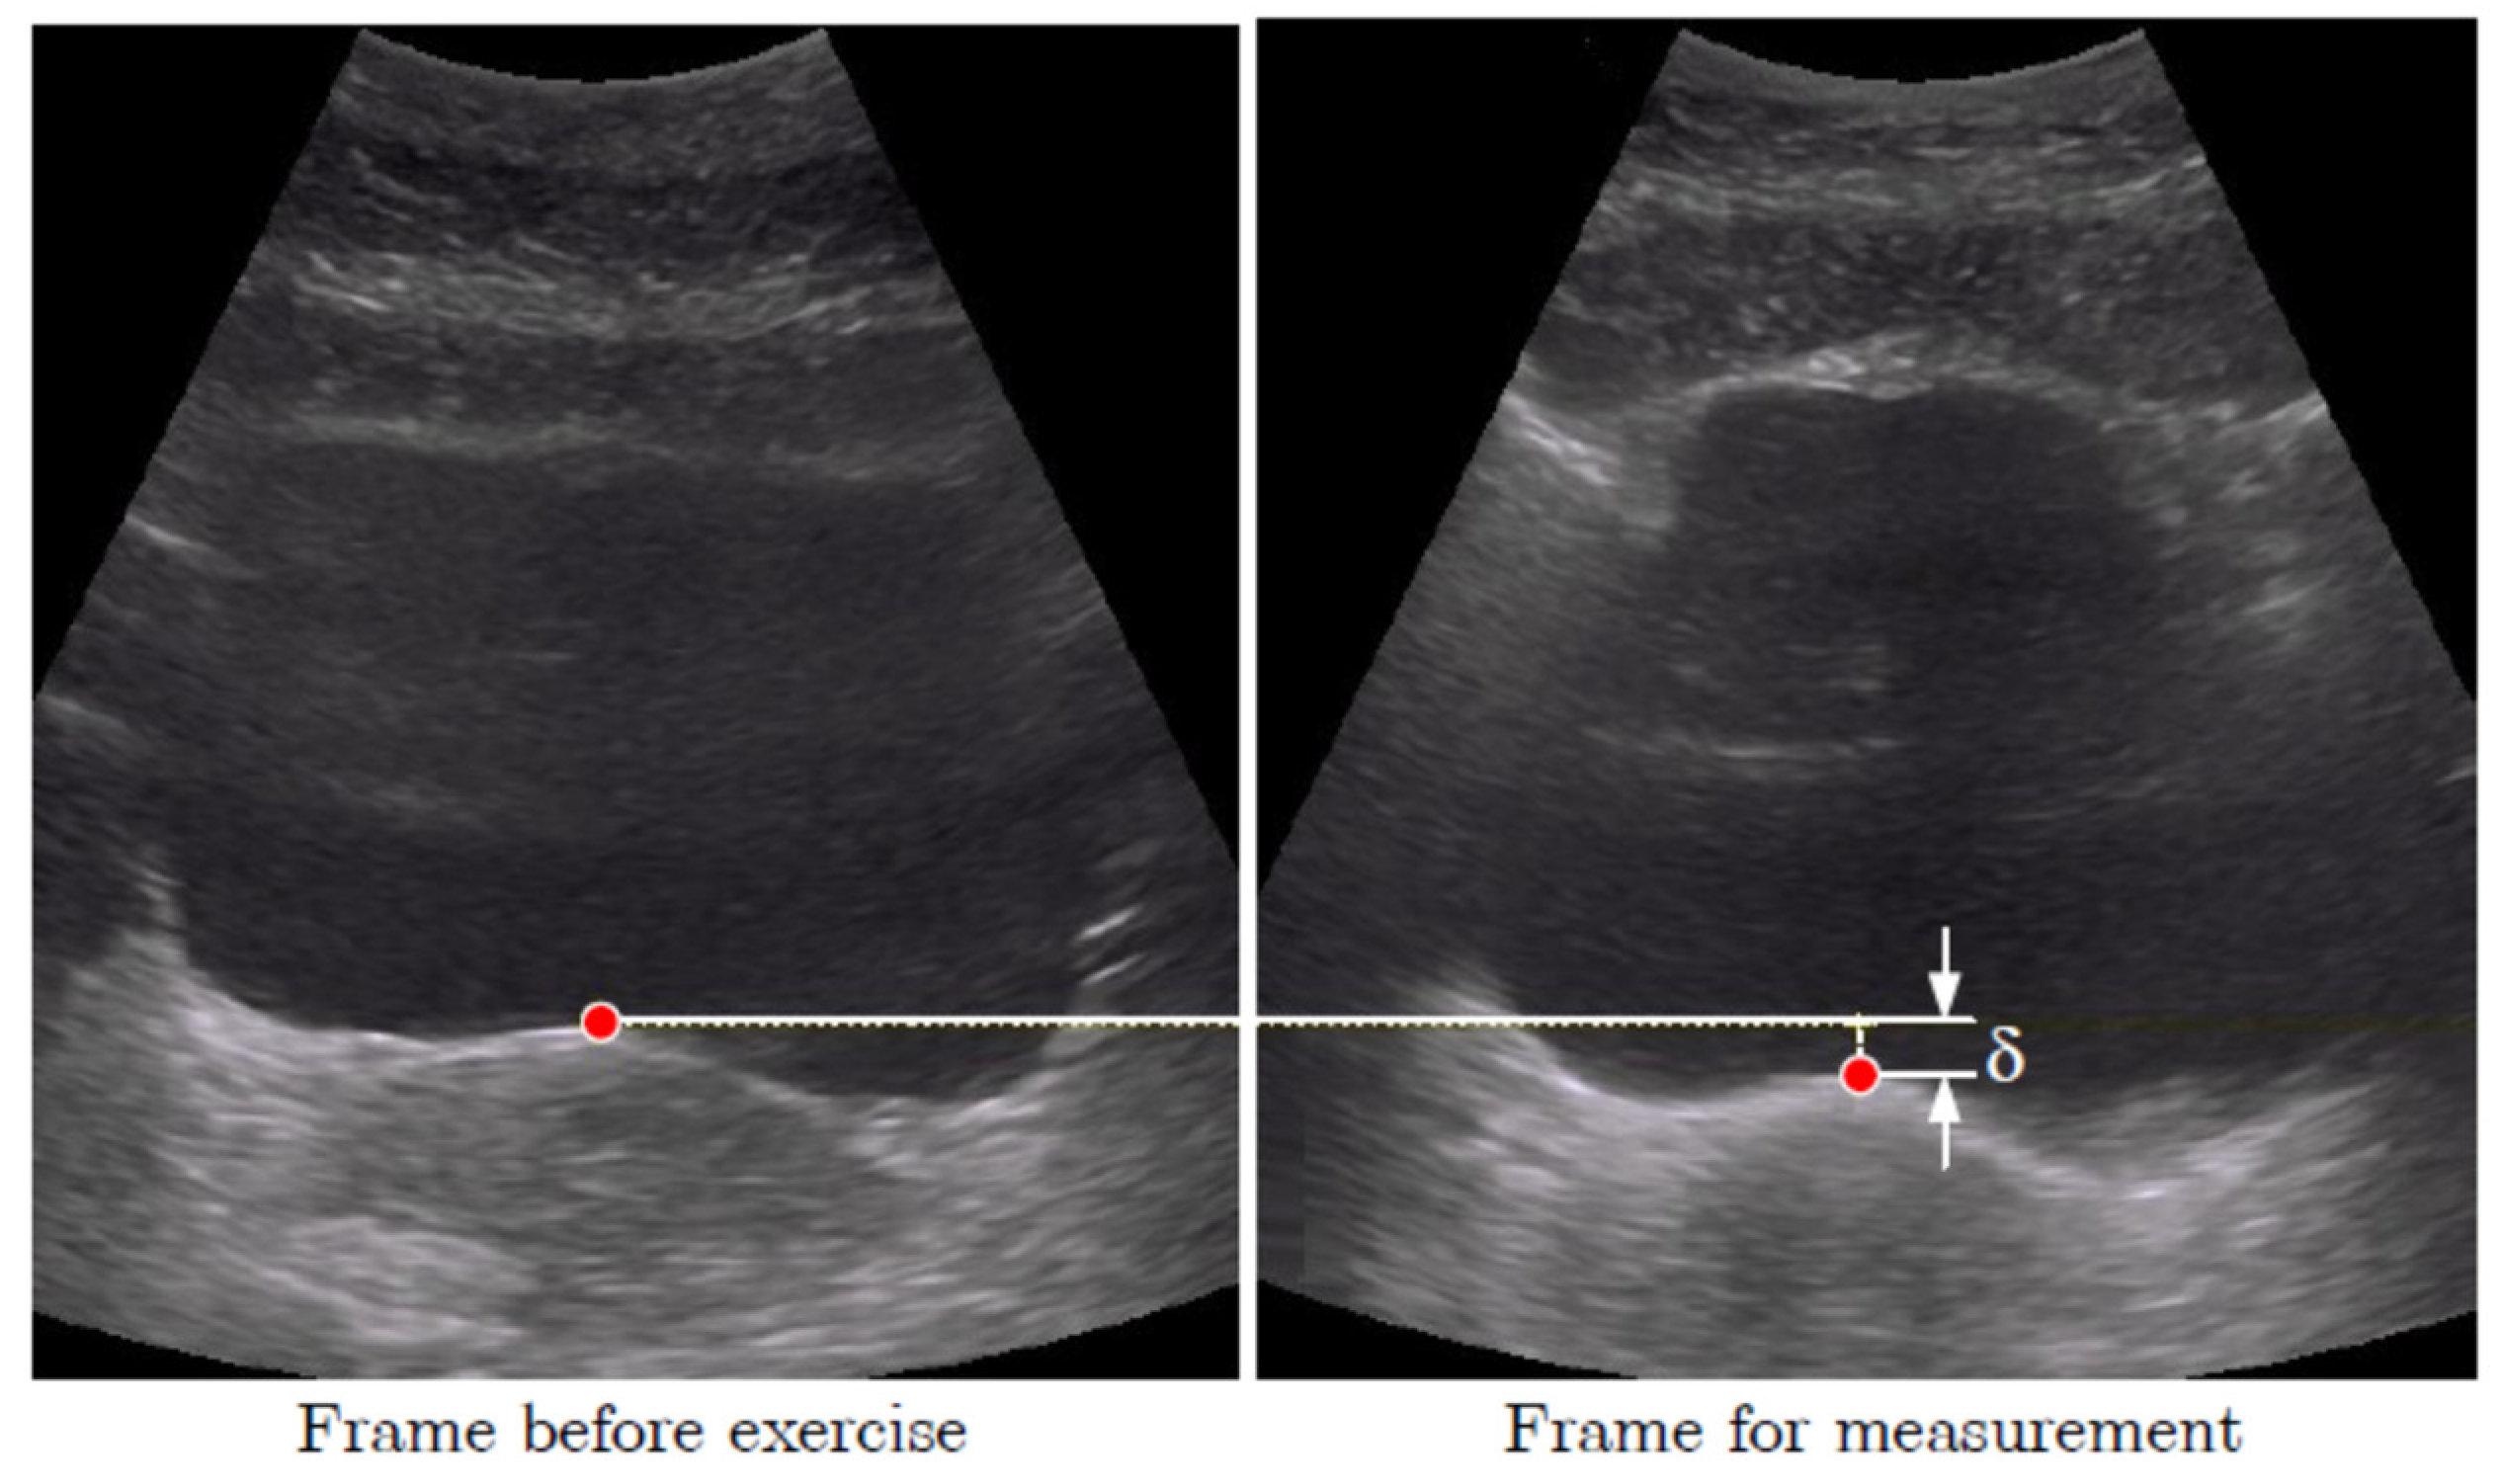

2.3. Data Processing